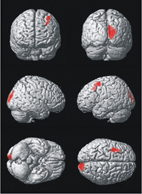

此外,我們也利用新的3D立體定向表面投影技術,及與資料庫中正常模組比較差異等技術,來增加檢查的準確性。

全面自動化立體影像校正

全腦部立體投影技術

▲自動與正常資料庫比對,標定代謝低下區域